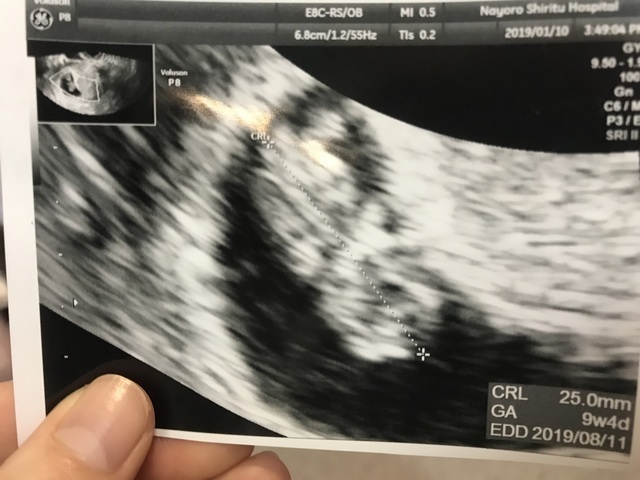

10週(10w・男の子)|ばんた さん(29歳)

エコー写真撮影時のエピソード:

五回目の妊娠で初めて30mm超え、順調と言われて感動した。 こんなに人のカタチにまでなったのも初めてだし、標準通りに成長することができてほんとよかった。

今は22週になり、順調に元気に育っており、胎動も感じられてこのまま無事産まれる事を祈ってます。